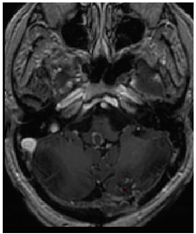

Three cases from the NTUH dataset showing representative results of different models were shown in Table 2, Table 3 and Table 4. The overall dice scores of these networks on the NTUH dataset ranged from 0.33 (DeepMedic) to 0.51 (V-Net). Table 5 shows the detailed performance of each network tested with the NTUH dataset.

Table 2. Predictions with low dice scores.

Ground truthDeconvNetDeepMedic

Applsci 11 09180 i001 Applsci 11 09180 i002 Applsci 11 09180 i003

PSPNetU-NetV-Net

Applsci 11 09180 i004 Applsci 11 09180 i005 Applsci 11 09180 i006